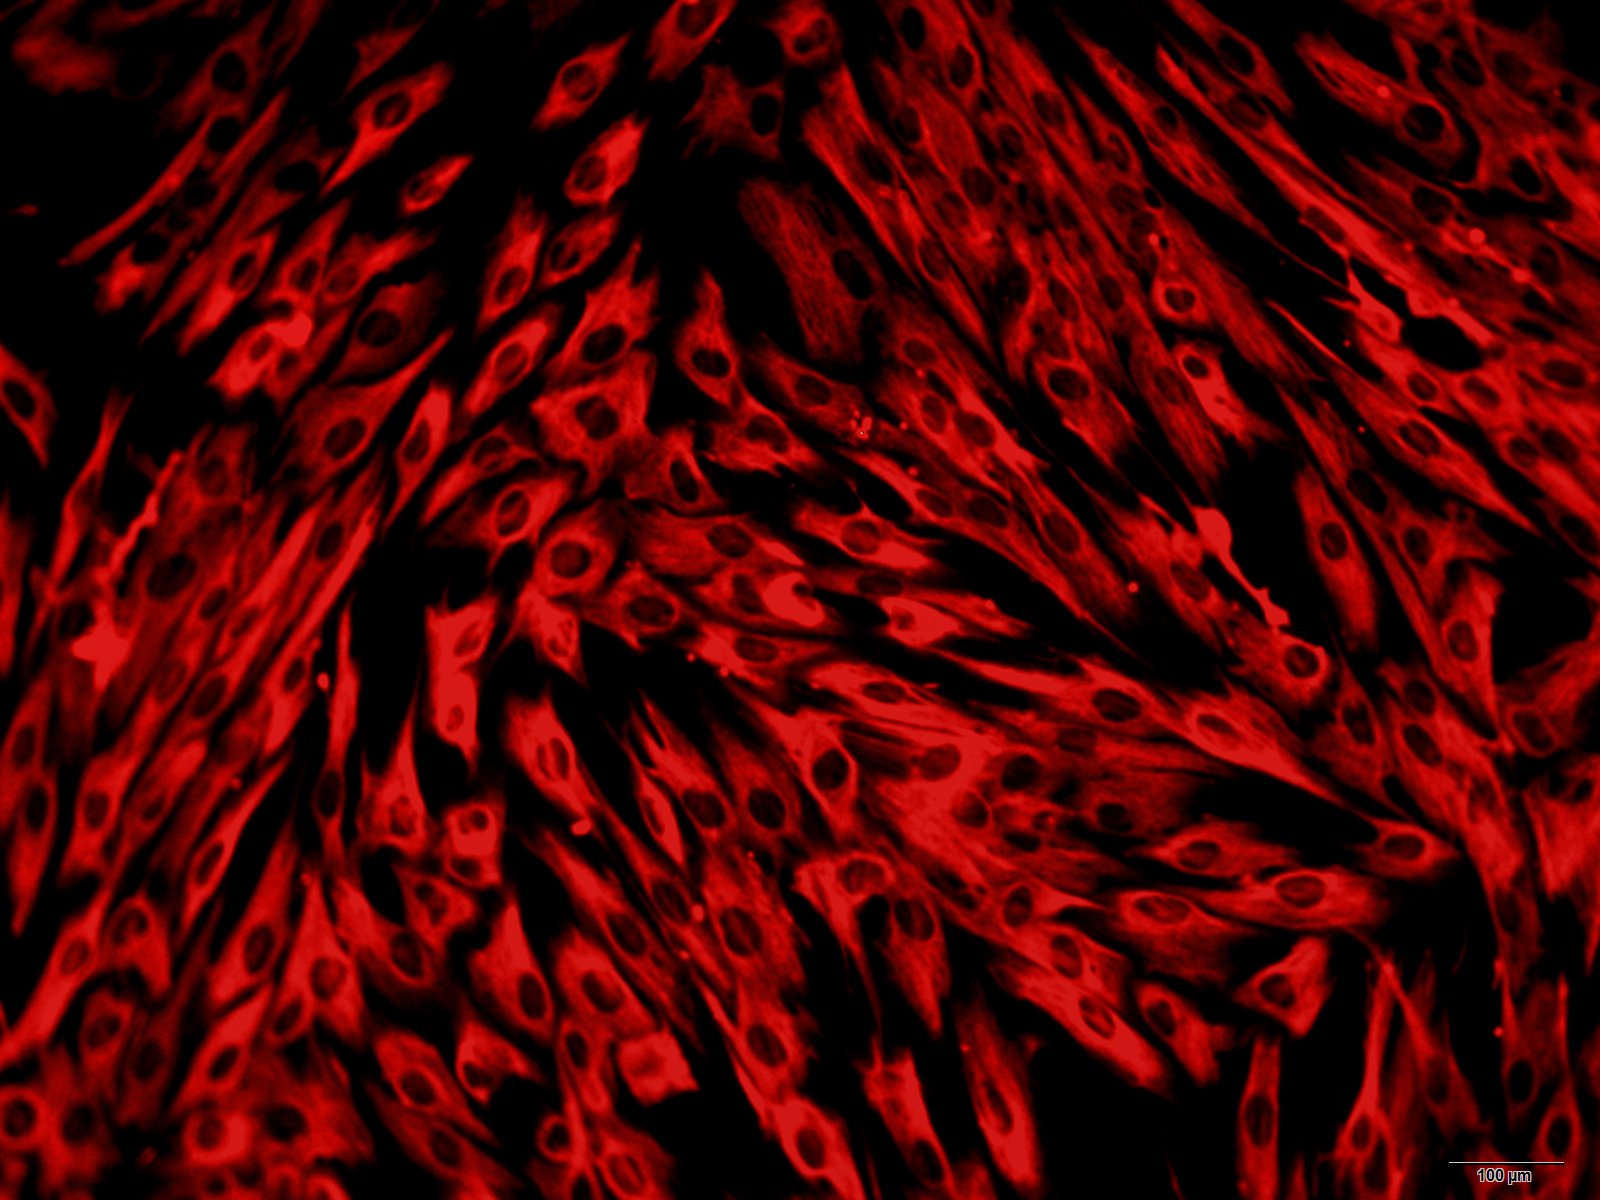

本公司生产的人肺泡巨噬细胞采用体外灌注法制备而来,细胞总量约为5×105/T25方瓶,CD68呈阳性,细胞纯度可达90%以上,且不含有HIV-1、 HBV、HCV、支原体、细菌、酵母和真菌等。

实验材料: 1. 肺泡巨噬细胞来源:体重为2—3kg的成年兔。也可使用成年大鼠; 2. 灌洗液:不含Ca2+ 和Mg2+ 的1×PBS,添加200000IU/L青霉素、200mg/L链霉素,pH7.4; 3. 培养液:MEM培养液,添加谷氨酰胺1mmol/L、卡那霉素100µg/ml、青霉素200IU/ml、链霉素200µg/ml、HEPES 10mmol/L和10%胎牛血清; 4. 无菌手术器械:手术刀、解剖剪、解剖镊、止血